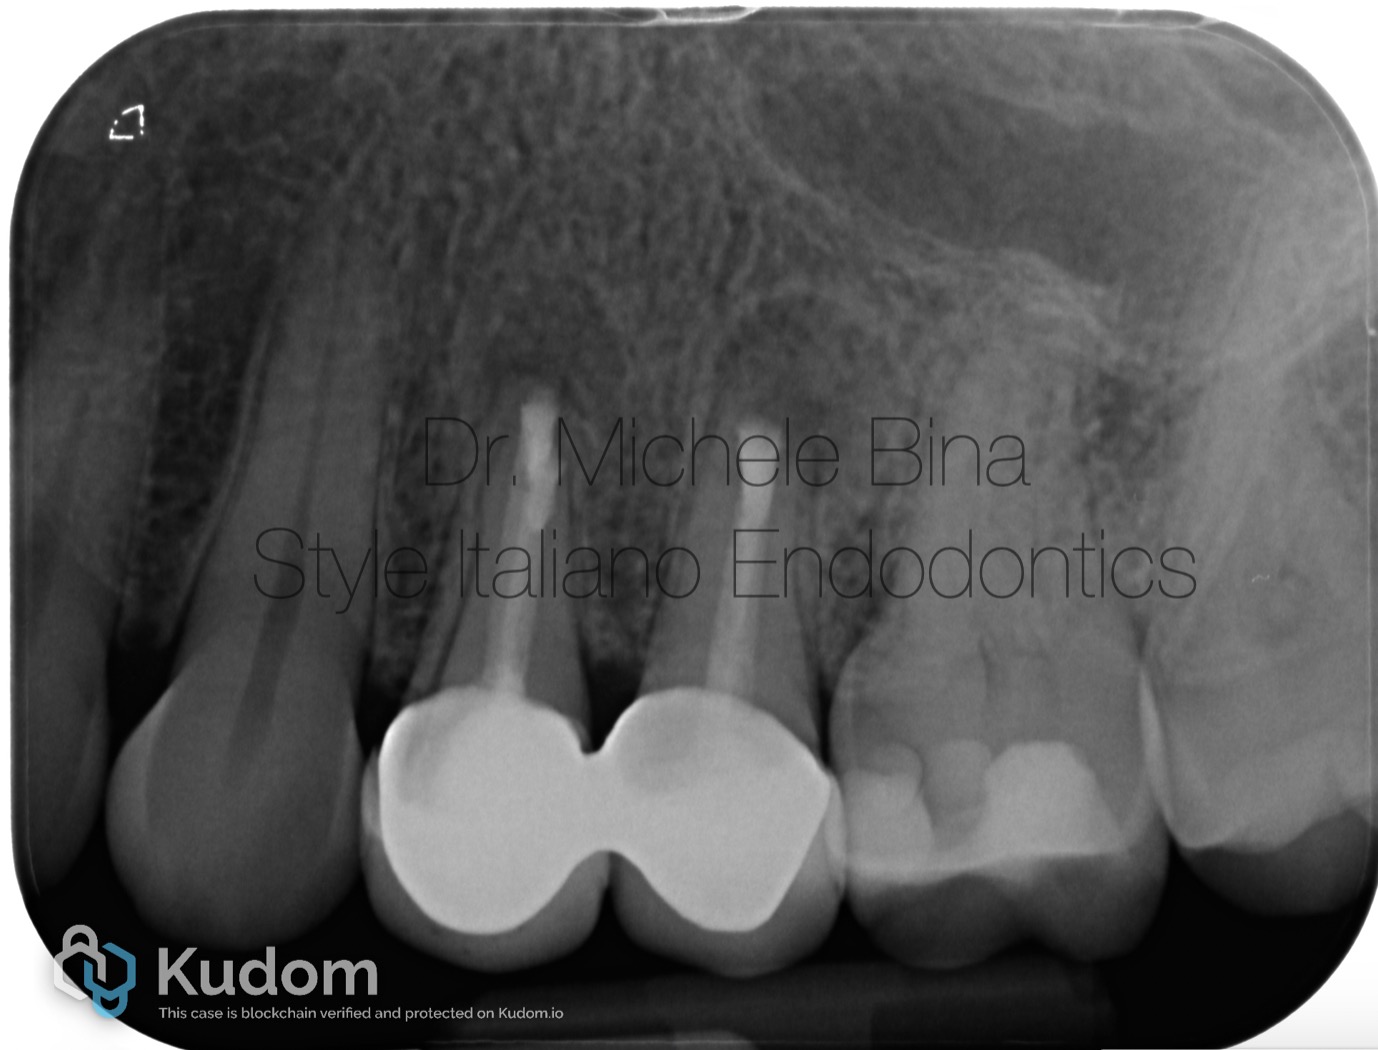

Fig. 4

Rx with follow up at 20 months with complete healing